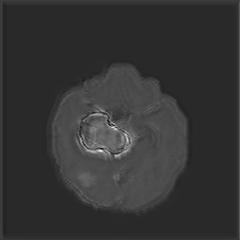

We argue that the sub-optimal paradigm of processing different abstractions within a single CNN pipeline can be remedied through the effective processing of information in a structured manner. Consequently, we devise strategies for disentangling the edge and texture information within a single training pipeline. Figure 2 illustrates how our proposed module, dubbed EG-CNN, can be paired with any existing CNN encoder-decoder to improve segmentation quality near intensity edges. We have applied our EG-CNN to the tasks of brain and liver tumor segmentation in medical images (Figure 3).

(1) Brain MR (2) Liver MR (3) Liver CT (4) Lung CT